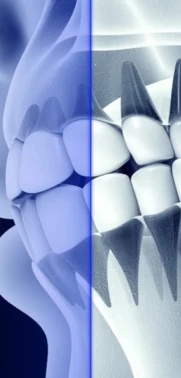

|  | Так выглядят металлические (слева на картинке) и керамические брекеты (справа) |